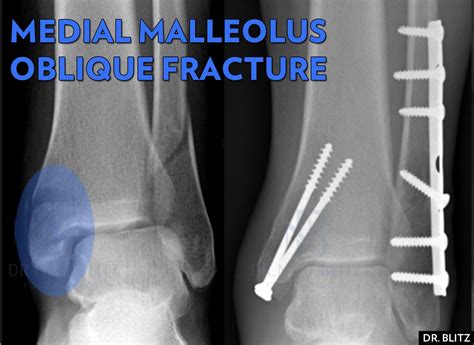

• X-Rays: X-rays are the primary imaging tool used to confirm the presence and extent of the fracture.

• Open Reduction and Internal Fixation (ORIF): A procedure where the bone fragments are realigned and held in place with screws, plates, or rods.